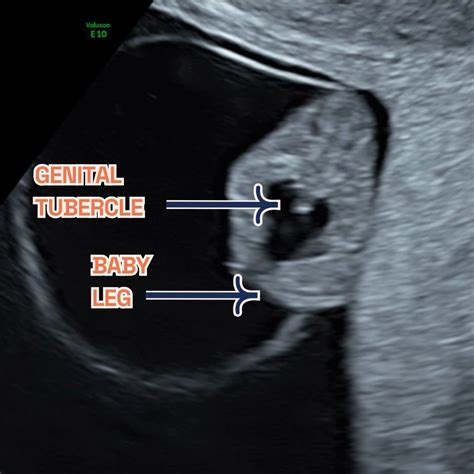

Can I Find Out the Baby's Gender?

At 9 weeks, it is too early to determine the baby's gender. The external genitalia have not yet developed enough to be visible on an ultrasound. Gender determination is typically possible around 18-20 weeks.